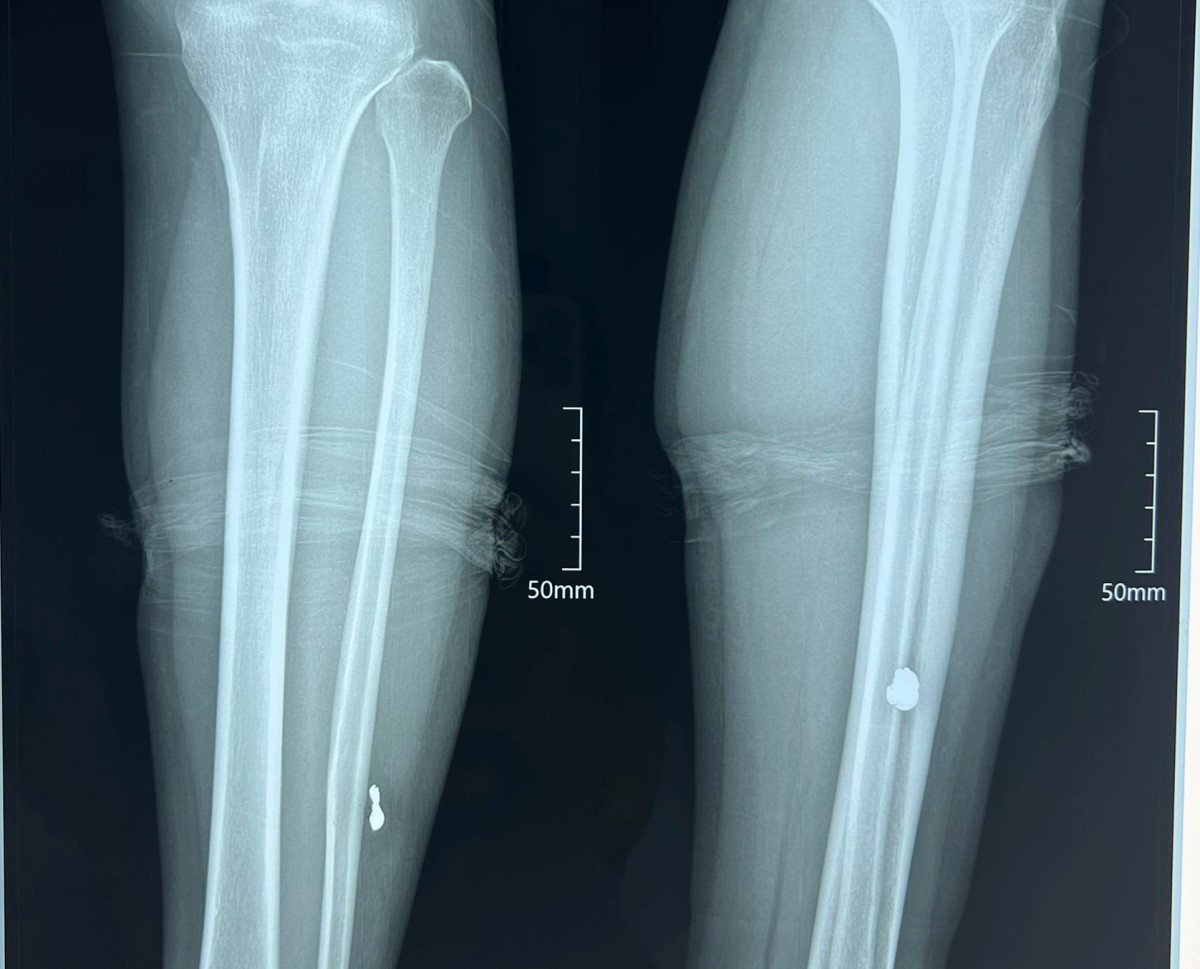

Người dân sống gần khu vực nghe tiếng súng nổ chạy đến và đưa hai chị đi cấp cứu tại Bệnh viện Đa khoa Phúc Hưng. Kết quả chụp phim cho thấy cả hai người đều có đầu đạn trong đùi và bắp chân.

Đến 13h chiều cùng ngày, hai nạn nhân đã được phẫu thuật lấy đầu đạn ra khỏi cơ thể, sức khỏe tạm thời ổn định.